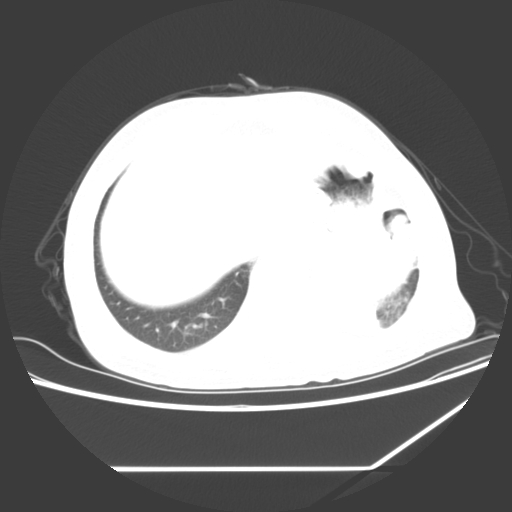

标题: CT25393:病人45岁,咳嗽,吐黄痰带血丝,发热,胸闷月余 [打印本页]

1、左肺中央型肺癌并双肺弥漫性转移   2、双肺部感染    3、肺大泡     4、左侧胸腔积液

双侧肺弥漫性病变,可见“空泡征”及“蜂窝征”,考虑肺泡癌可能性大,左侧胸腔积液,考虑胸膜受累可能!

考虑肺泡癌,建议排除感染。

考虑肺泡癌

1)不排除肺泡癌可能。2)左侧胸腔积液。